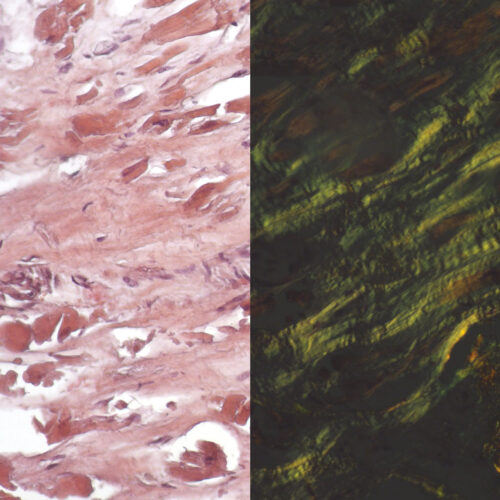

Congo Red Highman kit

Three-reagent kit for staining amyloids, characteristic for use of alkaline solution as differentiation medium in order to avoid undesirable non-specific coloration of cellular substances. Amyloid deposits display green coloration under polarized light.

Congo Red Puchtler kit

Three-reagent kit for staining amyloids, characteristic by its high ionic strength and pH enhancing the specificity of Congo Red dye binding to amyloid clusters. This method developed by Puchtler remains the gold standard for amyloids in tissue sections. Amyloid clusters have the property of double refraction that enables green coloration under polarized light.